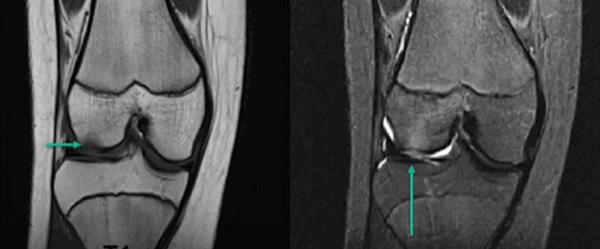

На МРТ хорошо прослеживаются все стадии этого процесса. На томограмме определяется выпот синовиальной жидкости и подхрящевая костная киста при остеоартрозе коленного сустава.

Фронтальный срез МРТ коленного сустава

МРТ коленного сустава показывает наличие кисты Бейкера в подколенной ямке (обозначена стрелкой)

На снимке - разрыв крестообразной связки и мениска вследствие травмы колена